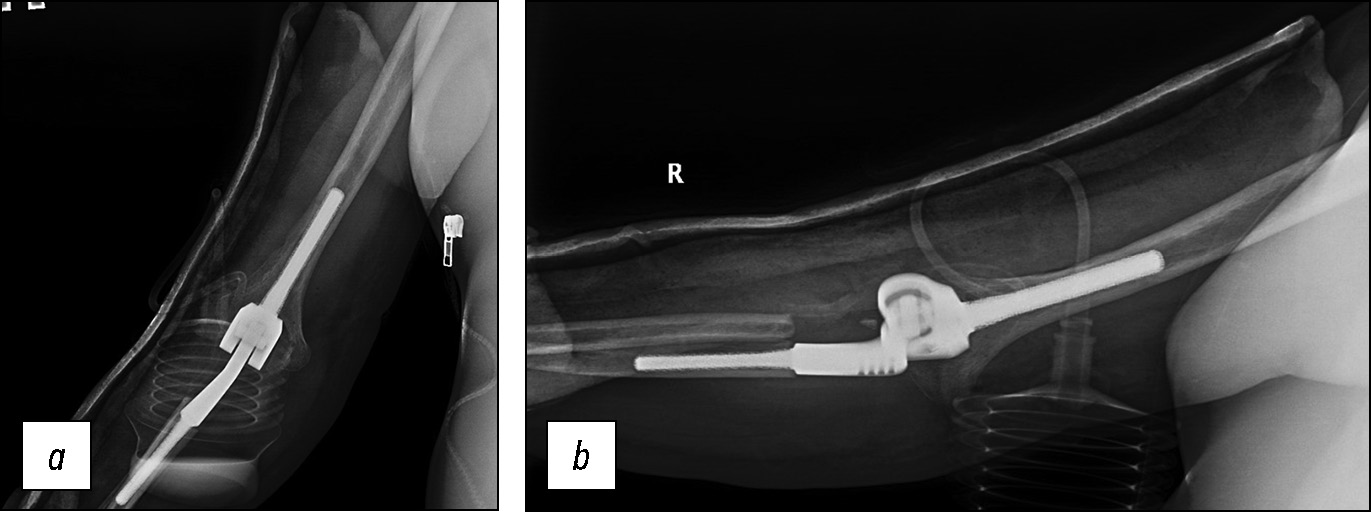

Послеоперационный период протекал без особенностей, выполнен рентген-контроль (рис. 16). Рана зажила первичным натяжением без признаков воспалительной реакции. Гипсовая иммобилизация снята через 4 недели с момента операции. После окончания срока иммобилизации начат курс ЛФК с целью восстановления амплитуды движений в локтевом суставе, увеличения тонуса мышц плеча.

Рис. 16. Пациент Д. Рентгенологический контроль после оперативного вмешательства: а — передне-задняя проекция, b — боковая проекция.

Fig. 16. Patient D. X-ray control after surgery: a — anterior-posterior projection, b — lateral projection.

Через 3 месяца болевых ощущений нет, отмечаются парестезии, незначительное ограничение амплитуды движения в области IV, V пальцев правой кисти. Результаты по шкалам Quick DASH, Oxford Elbow Score — 45 и 84 балла соответственно. Амплитуда движений в правом локтевом суставе: сгибание — 45 градусов, разгибание — 180 градусов, пронация — 90 градусов, супинация — 60 градусов (рис. 17, 18).